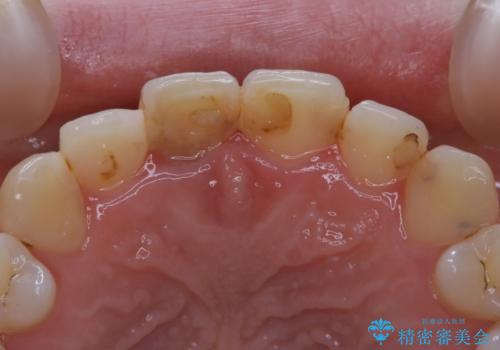

- 前歯一本だけ色が暗いことが気になりご相談にいらした患者様です。周辺の歯と色味をぴったり合わせることで自然な仕上がりになりました。

根管治療をした歯は神経のある歯と比較して強度が下がり、長期的に破折のリスクが高まると言われています。破折のリスクを軽減させるため、根管治療を行った歯に対しては歯冠をすべて覆うクラウンという被せ物にて補綴処置を行います。

適合不良の補綴物は二次的な虫歯発生のリスクが高まります。